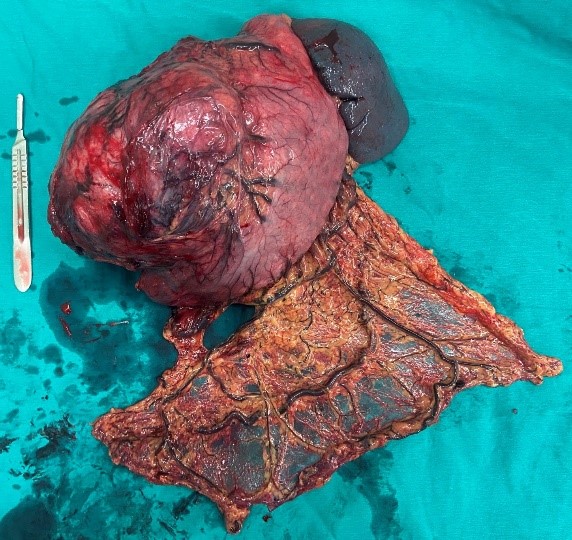

Hình 3: Hình ảnh khối GIST dạ dày kèm thân đuôi tụy và lách sau khi được lấy ra khỏi ổ bụng.

Bệnh nhân đã phải trải qua một cuộc phẫu thuật lớn: mổ mở cắt cả khối gồm toàn bộ dạ dày, thân đuôi tụy và lách, ca mổ phức tạp, tuy diễn ra thành công ngoài mong đợi nhưng chặng đường tiếp theo với anh N sẽ nhiều khó khăn, nguy cơ bệnh dễ tái phát hoặc di căn…

Trường hợp thứ nhất: Bệnh nhân N, nam 47 tuổi. Tiền sử viêm dạ dày nhiều năm, điều trị không thường xuyên. Khoảng 6 tháng gần đây, bệnh nhân thấy đau tức vùng thượng vị, hay đầy bụng, ăn uống kém hơn. Bệnh nhân tự mua thuốc điều trị viêm dạ dày nhưng không đỡ, đến khi tự sờ thấy khối ở vùng thượng vị mới quyết định đi khám tại Khoa Phẫu thuật Tiêu hóa – Gan mật tụy, Bệnh viện Bạch Mai và được chẩn đoán: GIST dạ dày, tuy nhiên khối u lớn, ở giai đoạn muộn nên đã xâm lấn vào thân đuôi tụy.